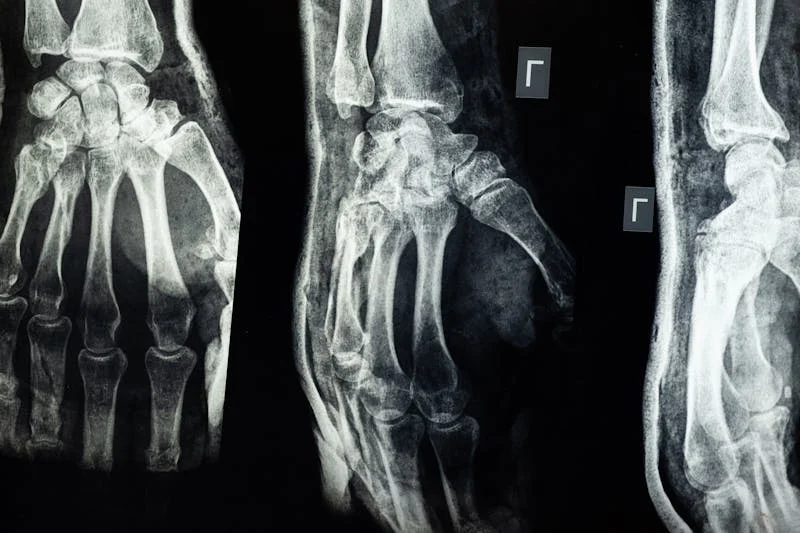

X-ray showing detailed view of hand bones representing fracture injury claims

How Fractures Are Diagnosed

Fractures are typically confirmed with X‑rays, CT scans, or MRI when soft‑tissue damage is suspected. Keep copies of imaging reports and follow all recommended treatment, as documentation is critical in proving damages.